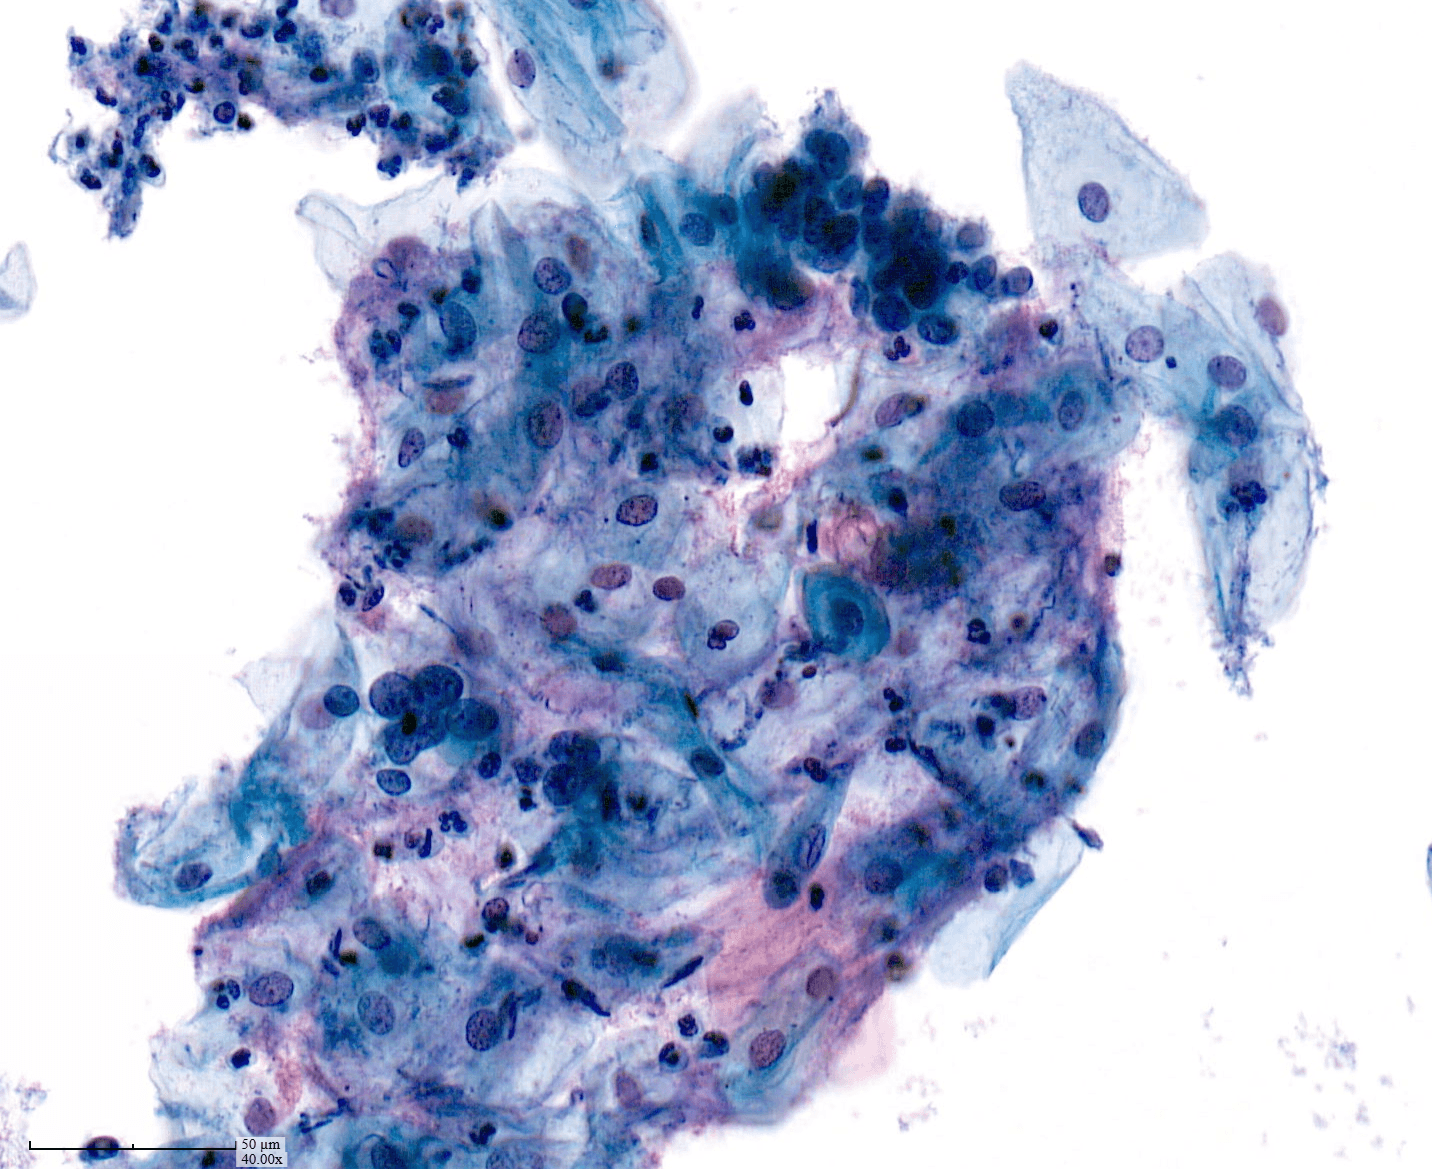

CytoProcessor® is a revolutionary AI-powered system that brings digital cytology to the forefront of cervical cancer screening. It uses powerful AI algorithms to automatically analyze digitized cytology slides, rapidly identifying and classifying abnormal cells.

CytoProcessor® is a revolutionary AI-powered system that brings digital cytology to the forefront of cervical cancer screening. It uses powerful AI algorithms to automatically analyze digitized cytology slides, rapidly identifying and classifying abnormal cells.

This smart system prioritizes the most diagnostic relevant cells, allowing pathologists and cytotechnologists to focus on what matters most. With CytoProcessor®, you can say goodbye to the microscope and hello to a faster, more accurate, and more comfortable workflow.

This smart system prioritizes the most diagnostic relevant cells, allowing pathologists and cytotechnologists to focus on what matters most. With CytoProcessor®, you can say goodbye to the microscope and hello to a faster, more accurate, and more comfortable workflow.

Clinical Leadership

With a diagnostic sensitivity of 96%, CytoProcessor® significantly enhances the accuracy of medical diagnostics, reducing missed cases by a factor of 2.6. At the same time, it boosts diagnostic efficiency by up to threefold, ensuring patients receive results with the fastest possible turnaround time.

Clinical Leadership

With a diagnostic sensitivity of 96%, CytoProcessor® significantly enhances the accuracy of medical diagnostics, reducing missed cases by a factor of 2.6. At the same time, it boosts diagnostic efficiency by up to threefold, ensuring patients receive results with the fastest possible turnaround time.

Clinical Leadership

With a diagnostic sensitivity of 96%, CytoProcessor® significantly enhances the accuracy of medical diagnostics, reducing missed cases by a factor of 2.6. At the same time, it boosts diagnostic efficiency by up to threefold, ensuring patients receive results with the fastest possible turnaround time.